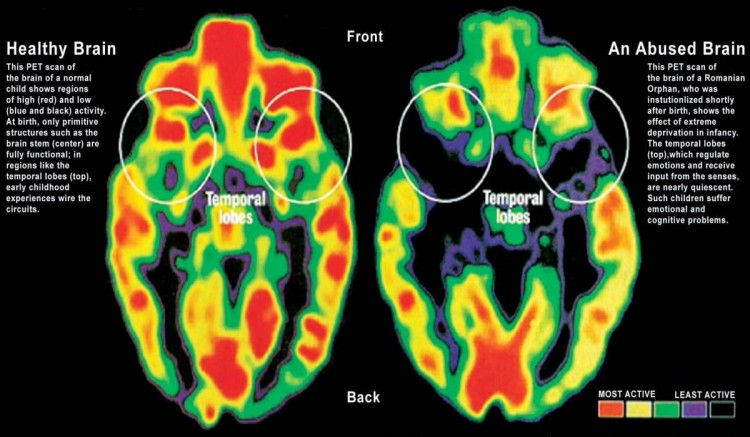

Low Self-Esteem: Persistent abuse can create lasting feelings of worthlessness that might take years to overcome. Oh man, I had no self-esteem when I left. I felt like nothing. And didn't help how others treat you when you leave relationships that were predominately mental and emotionally abused based. no scars so people can see the damaged that happened. but they were there, just tucked in my mind. my brain changed from it. Sadly no one sees that unless you have stamped on you your MRIs of how your brain changed.